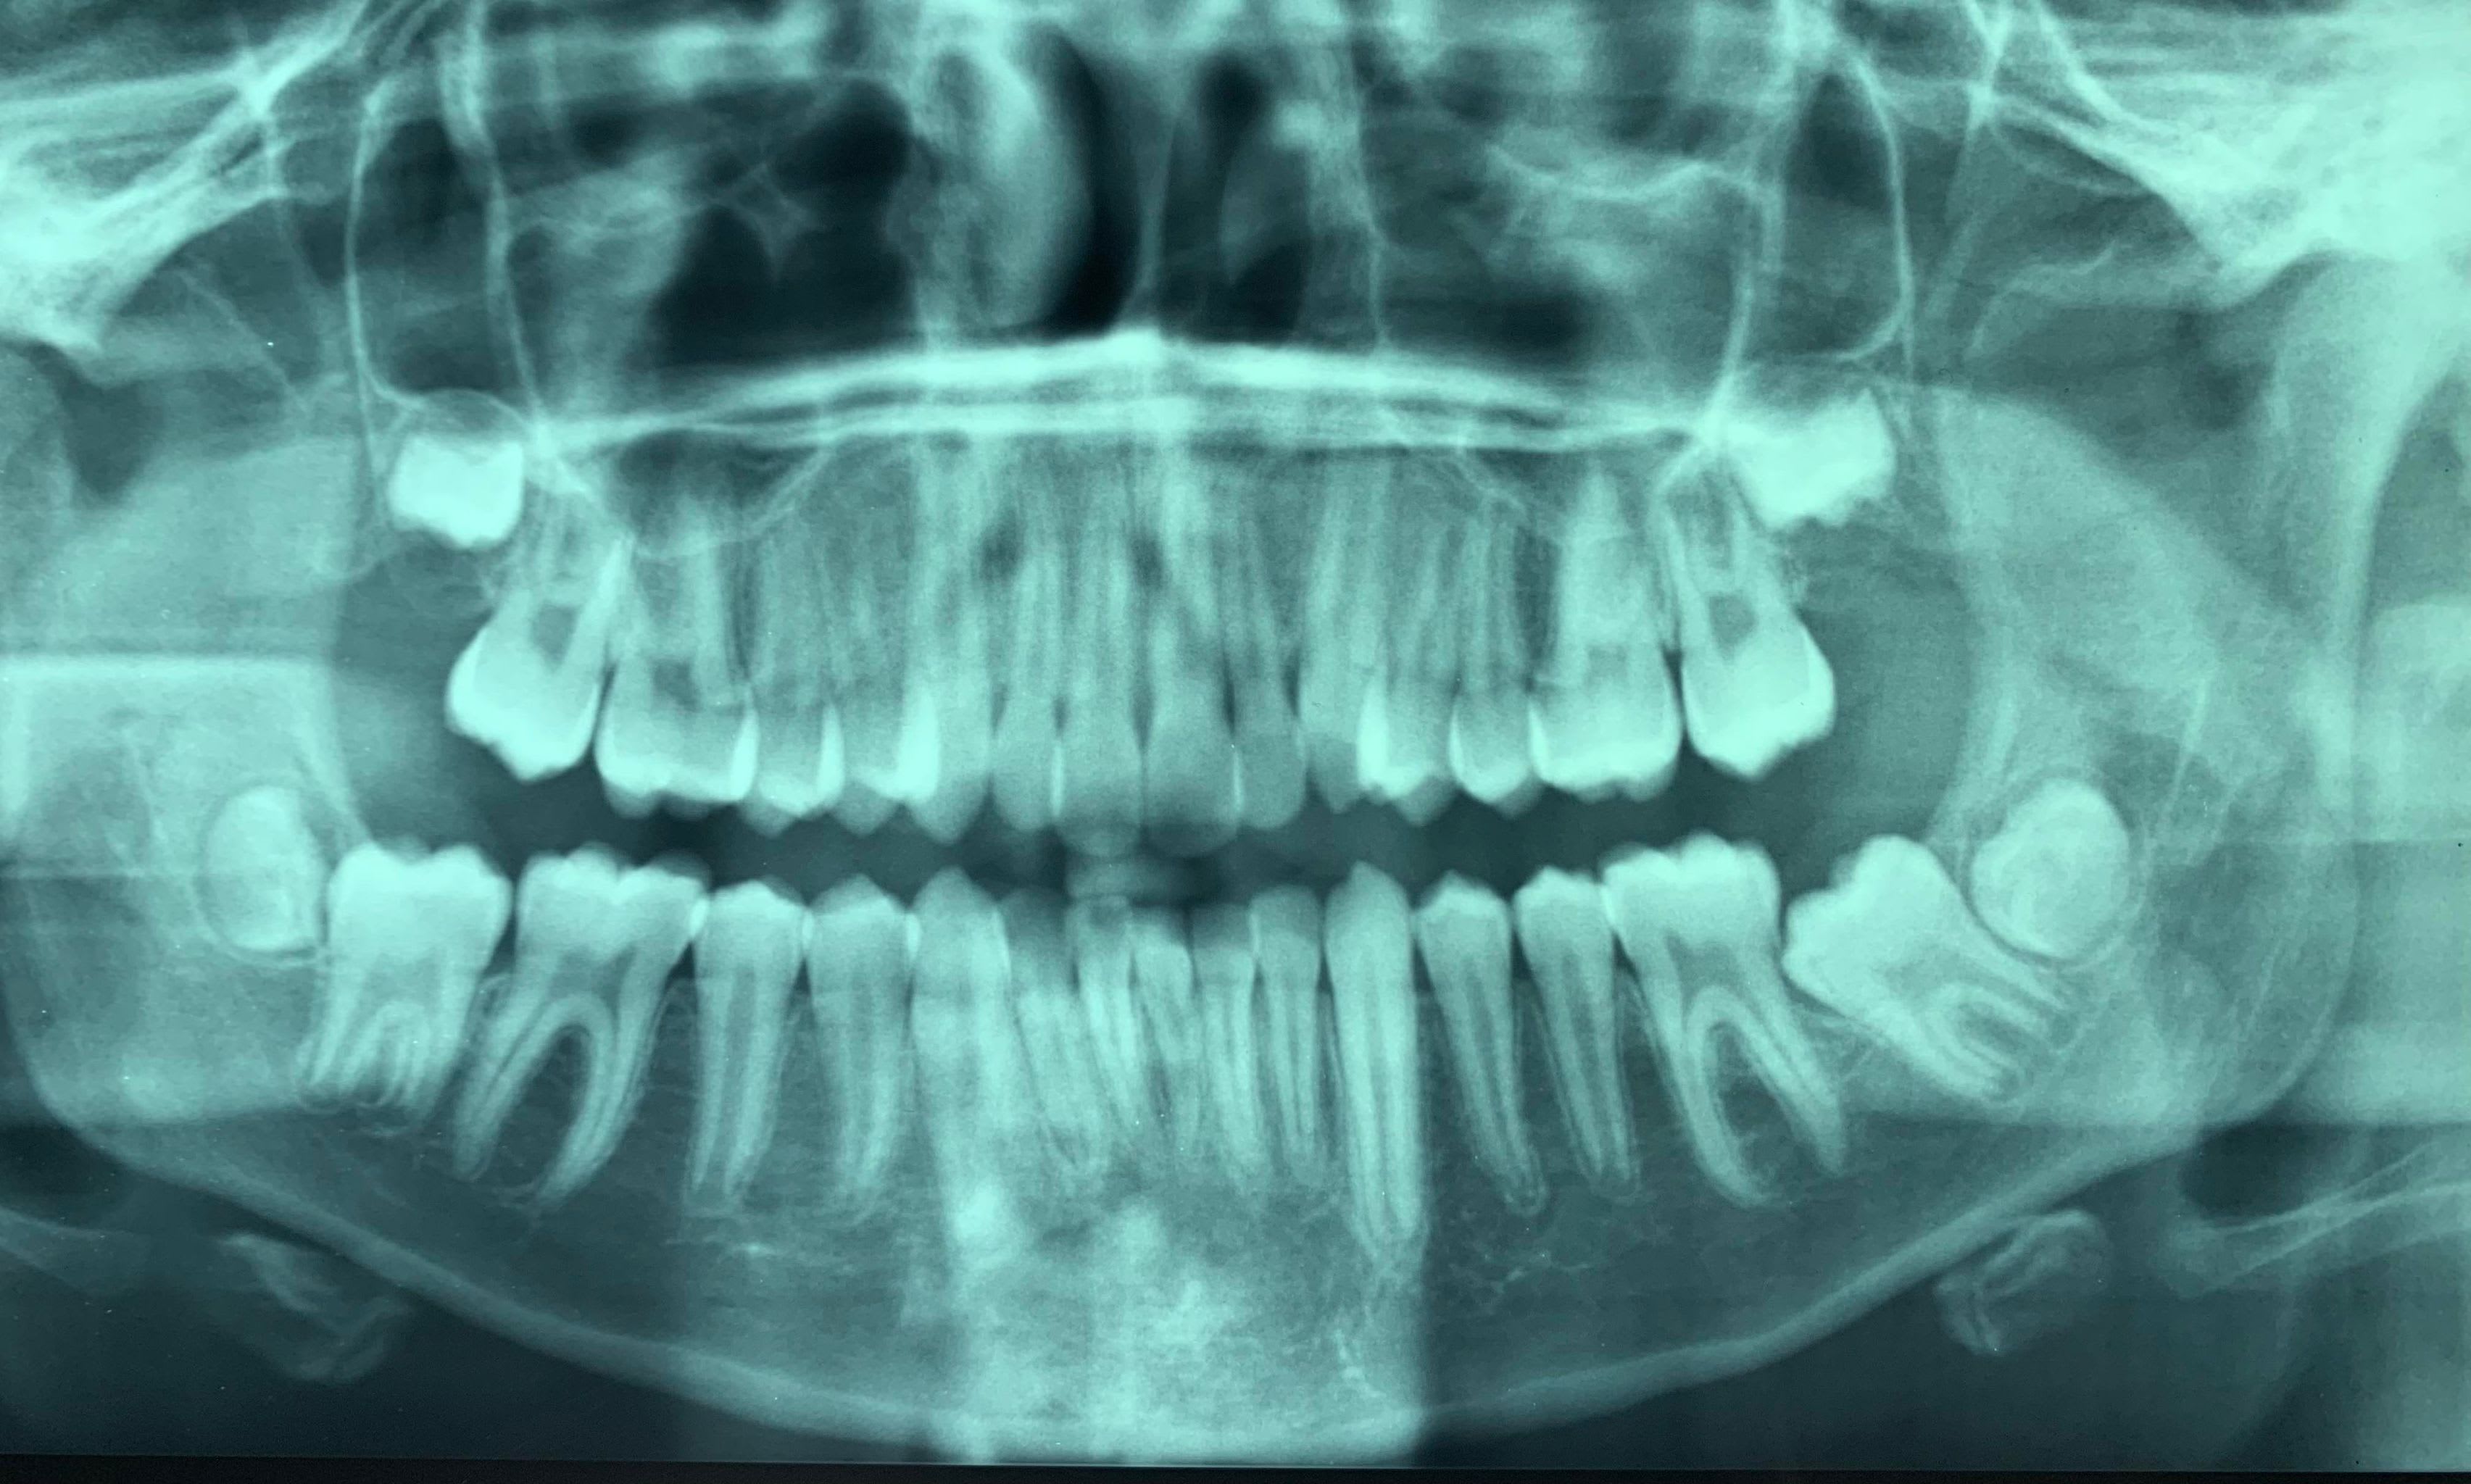

En ce dimanche studieux je sollicite une nouvelle fois vos avis sur ce plan de traitement orthodontique concernant un cas d'incisive surnuméraire.

Le patient :

- 11 ans et 10 mois

- Normodivergent (tendance hypo)

- déglutition atypique

- interposition labiale inférieure inter arcade

- classe I squelettique

- classe II molaire et canine

- encombrement antérieur maxillaire

- Présence d'une incisive surnuméraire mandibulaire : responsable d'une déviation des milieux incisifs, d'un léger encombrement mais surtout camouflé par une proalvéolie importante IMPA 111°.

Bien que l'encombrement n'est pas monstrueux, je partirais quand même sur l'extraction de l'incisive la plus centrale (marquée d'une croix sur les moulages) afin d'espérer un correction de la position de l'incisive mandibulaire actuellement en proalvéolie, une légère mésialisation des secteurs postérieurs (favorable à la correction de classe II et aussi à l'évolution de la 37 actuellement retenue contre la 36). Pour la correction de la classe II soit commencer par un système carrière qui m'ouvrirait des petits espaces pour traiter l'encombrement maxillaire puis poursuite par un traitement multiattache avec utilisation d'élastiques de classe II.